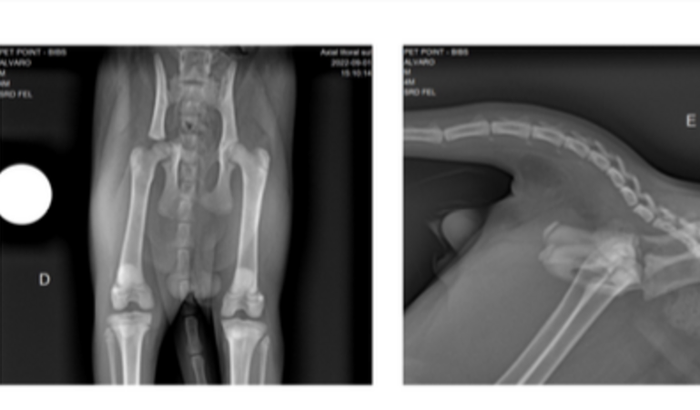

Cirurgia do Bibs

Eu sou o Alvaro, meu gatinho foi atropelado e precisa de cirurgia. Infelizmente não consigo arcar com todos os custos. Decidi abrir uma vaquinha para salvar o Bibs! ver tudo

Eu sou o Alvaro, meu gatinho foi atropelado e precisa de cirurgia. Infelizmente não consigo arcar com todos os custos. Decidi abrir uma vaquinha para salvar o Bibs!